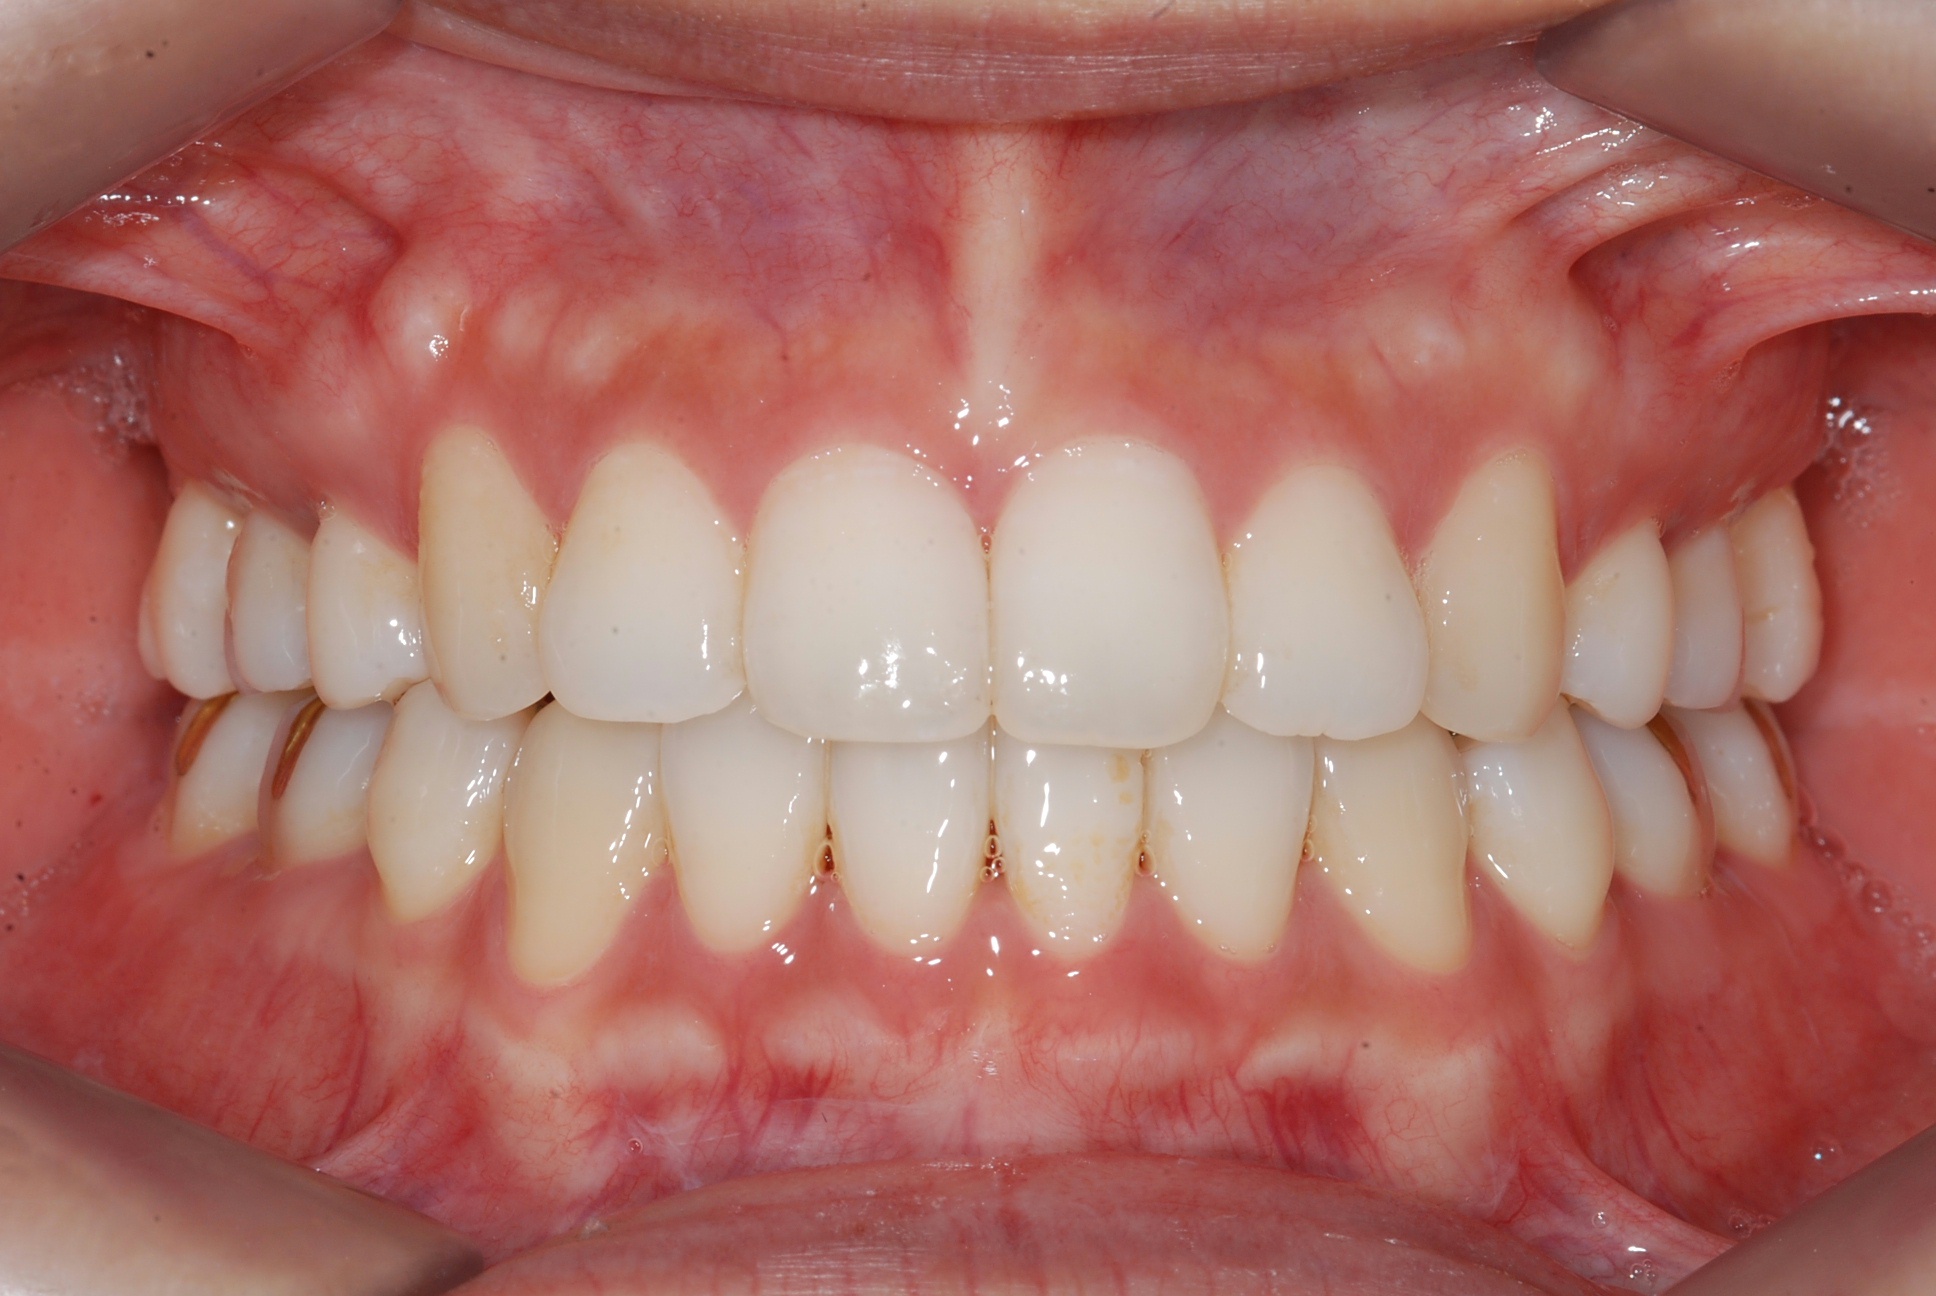

치료 후 사진입니다.